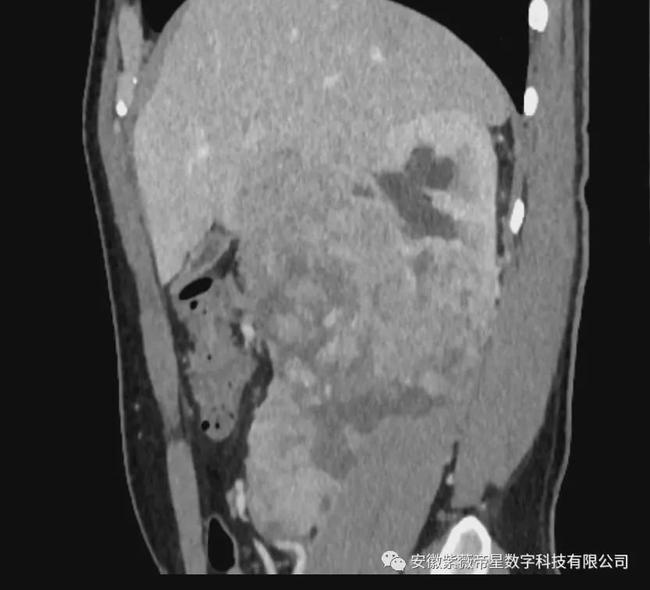

矢状面

临床病史: 患者男,35岁,右肾区疼痛三月余,入院检查CT显示,右肾中下极见巨大软组织密度团块影,长度约14.8cm,其内密度不均匀,增强扫描明显强化,与右侧肾盂、肾盏及输尿管移行部分界不清,贴近临近肝脏、下腔静脉。右侧肾盂、肾盏扩张、积水。右肾未见明显异常强化。